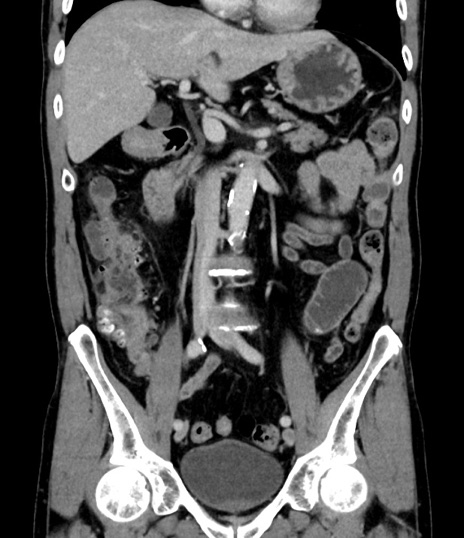

症例8(冠状断像)

【症例】 60歳代男性

【主訴】 黒色吐物

【現病歴】 4日前から嘔気自覚、2日前の朝食後にも嘔気あり、自分で手で嘔吐反射起こし嘔吐したところ血が混ざっていたため受診。

【既往歴】 5年前汎発性腹膜炎を伴う急性虫垂炎で手術、高血圧、前立腺肥大症、高脂血症

【身体所見】 腹部正中に手術癩痕あり 腹部平坦・軟圧痛なし膨満感あり

【データ】WBC 8400、CRP 4.54